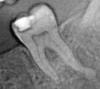

Лара3 Опубликовано 26 октября, 2013 Автор Поделиться Опубликовано 26 октября, 2013 до депульпирования Ссылка на комментарий

x3m Опубликовано 26 октября, 2013 Поделиться Опубликовано 26 октября, 2013 (изменено) Под мост, видимо Лапа, а Вам делали прицельные снимки этого зуба?А то этот нечитабелен... Изменено 26 октября, 2013 пользователем x3m Ссылка на комментарий

Лара3 Опубликовано 27 октября, 2013 Автор Поделиться Опубликовано 27 октября, 2013 А сколько каналов на этом снимке Вы видите? видно только 2, и я не разбираюсь Ссылка на комментарий

x3m Опубликовано 27 октября, 2013 Поделиться Опубликовано 27 октября, 2013 Учитывая вопрос в теме и предоставленный снимок, я могу утверждать с высокой долей вероятности, что каналов в Вашей семерке от двух до пяти. 1 Ссылка на комментарий

Лара3 Опубликовано 28 октября, 2013 Автор Поделиться Опубликовано 28 октября, 2013 Врач которому ходила сегодня по снимку предположил что кончик инструмента в одном из каналов, белая полоса прямо на верхушке зуба, на снимке на канале с левой стороны.... Ссылка на комментарий